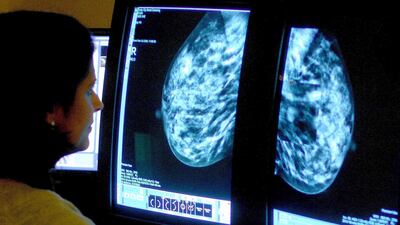

Statistics reveal that the most common forms of the disease are breast, lung, colon and rectum, and prostate cancers.